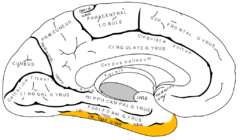

脳の構造 大脳を4つの領域に分けるランドマーク

脳の構造 大脳を右脳と左脳に分ける脳の溝